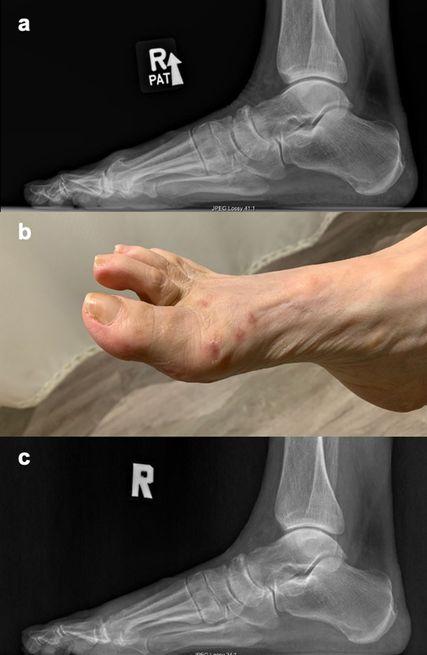

Abb. 1: 72-jährige Patientin mit Hallux rigidus und prominentem dorsalem Osteophyten mit guter Beweglichkeit im MTP-Gelenk: a) präoperatives Röntgenbild lateral belastend, b) 12 Wochen postoperativ nach perkutaner Cheilektomie; keine Schwellung, minimale Narben, c) Röntgenbild 12 Wochen postoperativ

Mit einer Beaver-Blade wird dorsal proximal zum palpablen Osteophyten und zentral über dem MT1 eine Inzision gesetzt. Dabei wird der Verlauf des sensiblen dorsomedialen Nervenastes beachtet. Mit dem Freer werden Weichteilgewebe abgeschoben und die Gelenkskapsel wird nach medial und lateral mobilisiert. Ein 2x20mm-Fräsenaufsatz wird eingebracht und die dorsale Cheilektomie durchgeführt. Ebenso wird der Osteophyt an der PP entfernt. Unter Röntgenkontrolle wird die Position der Fräse verifiziert. Nach Resektion des Knochens werden ein dorsomediales und dorsolaterales Portal zur GZGG-Arthroskopie gesetzt. Mit einer weichgewebeschonenden Technik wird eine 2.9-Optik eingeführt und mit einem 3.5-Shaver der Debris entfernt. Sind noch knöcherne Unebenheiten zu sehen, können diese unter direkter Visualisierung mit der Fräse entfernt werden (Abb. 1).